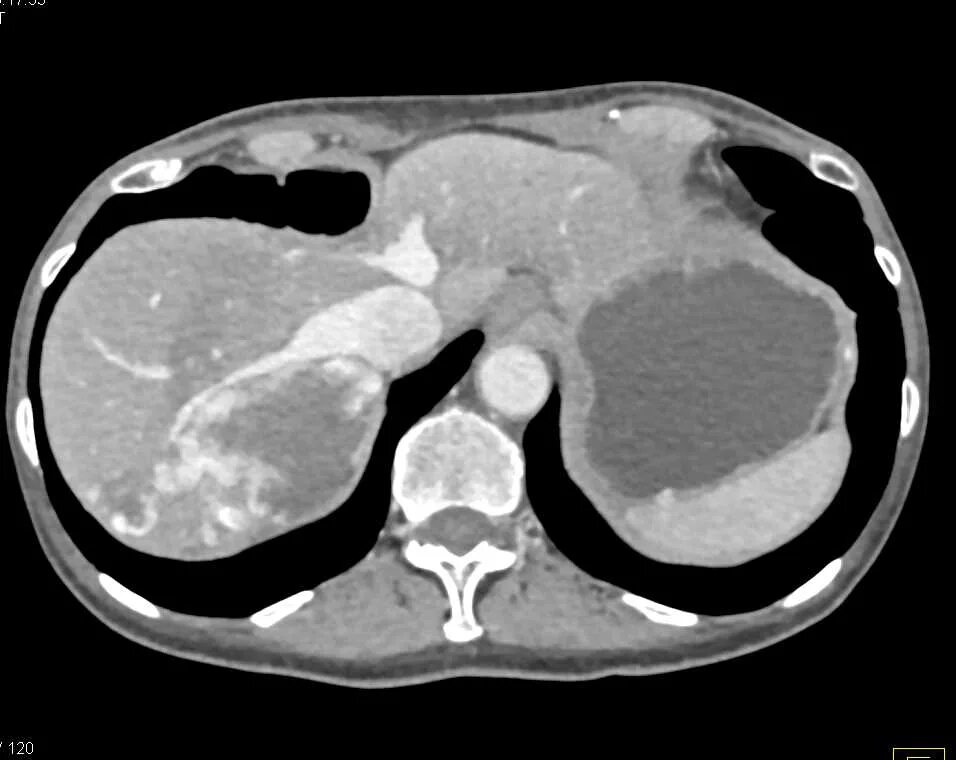

Народное лечение гемангиома печени